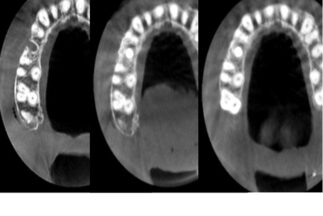

| 治療内容 | 上顎右側5相当部へインプラント埋入と同時にチタンメッシュを用いて自家骨と骨補填材による骨増生術を行った |